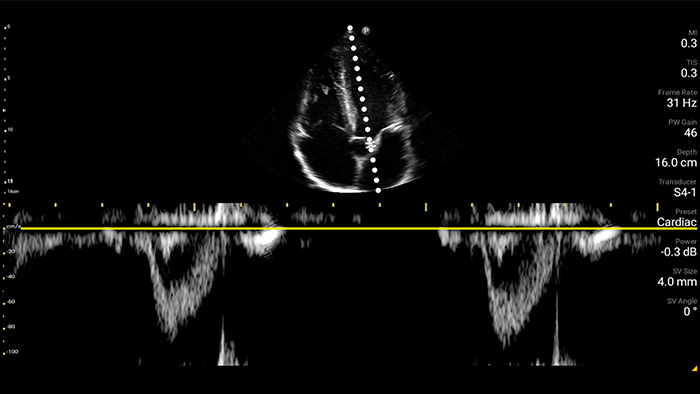

Exceptional ultrasound imaging

Lumify handheld ultrasound offers images that enhance diagnostic confidence.

See more when it counts

Lumify can help you make real-time decisions with more confidence, from assessment to recovery. Reveal the subtle details of an image, uncover enriched tissue definition with multiple angles and much more.